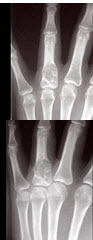

6、单项选择题

男,19岁,双手肿痛2年,晨僵,结合图像,最可能诊断是()

A.痛风

B.强直性脊柱炎

C.类风湿关节炎

D.退行性关节炎